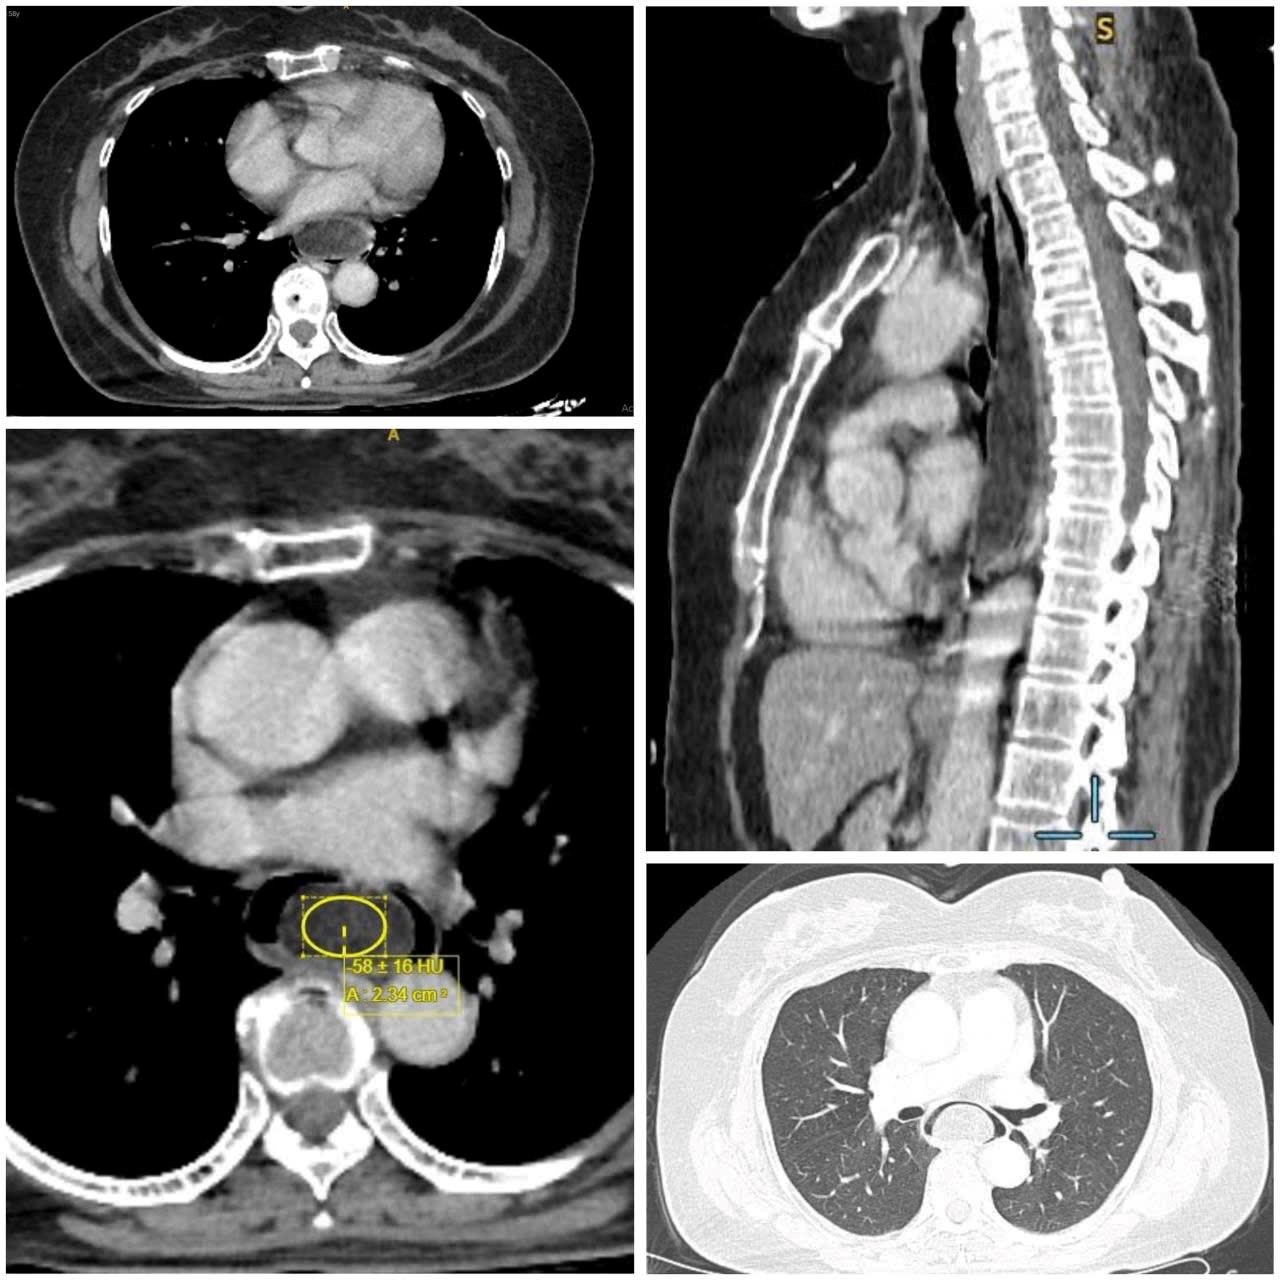

Kết quả nội soi và siêu âm nội soi cho thấy người bệnh có u mỡ thực quản dưới niêm mạc kích thước 16 x 3,5 x 3 cm – mức kích thước được đánh giá là “khổng lồ”, trong khi đa số khối u dưới niêm mạc đường tiêu hóa thường nhỏ hơn 3 cm.

TS.BS Bùi Ánh Tuyết, Trưởng khoa Nội soi - Thăm dò chức năng cho biết đây là ca bệnh hiếm gặp, chỉ chiếm khoảng 0,03% các trường hợp u tân sinh thực quản. Bác sĩ cho biết thêm nếu khối u tiếp tục phát triển, bệnh nhân có thể đối mặt với suy dinh dưỡng và nguy cơ chèn ép đường thở do u có cuống di động, thậm chí có thể dẫn đến nguy hiểm tính mạng.